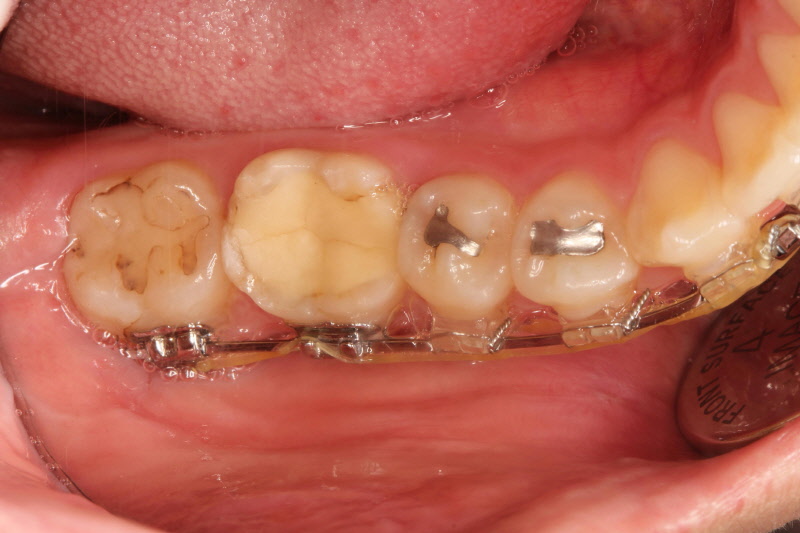

그러나 환자뿐 아니라 취급자 또한 불안할 수밖에 없습니다. 오랜 기간에 걸쳐 취급하게 된다면 안전을 장담할 수만은 없을 것입니다. 요즘은 방식이 개선되어 수은의 직접적 접촉이 별로 없는 방식으로 바뀐 제품도 있지만 수은에 대해서는 항상 논란이 이어지고 있습니다. 또한 시간이 지나면서 약간 아말감의 형태가 변형되며 주변부부터 부스러지거나 중간이 파절되고 금이 가기도 합니다. 재료 자체의 수명이 긴 편은 아닙니다. 그리고 치아의 내부를 검게 변색시키는 문제를 야기할 수도 있습니다.

오래되다 보면 금이가고 주변부부터 부스러짐